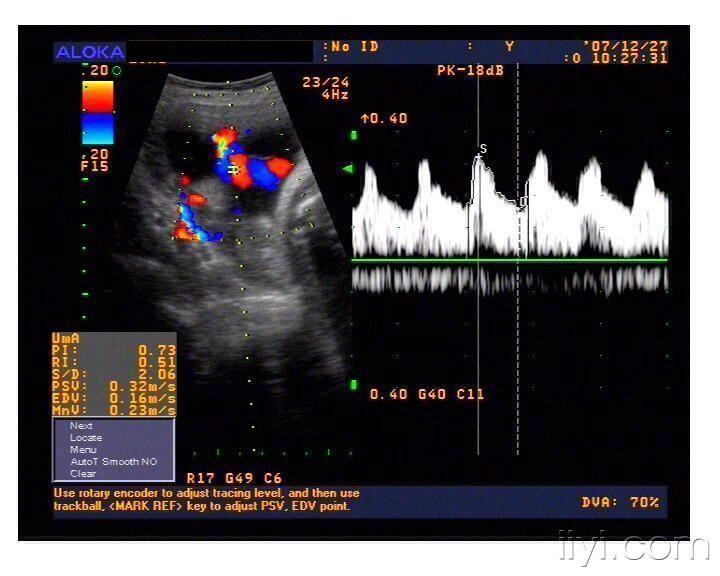

脐动脉

四维彩超发现单脐动脉一例